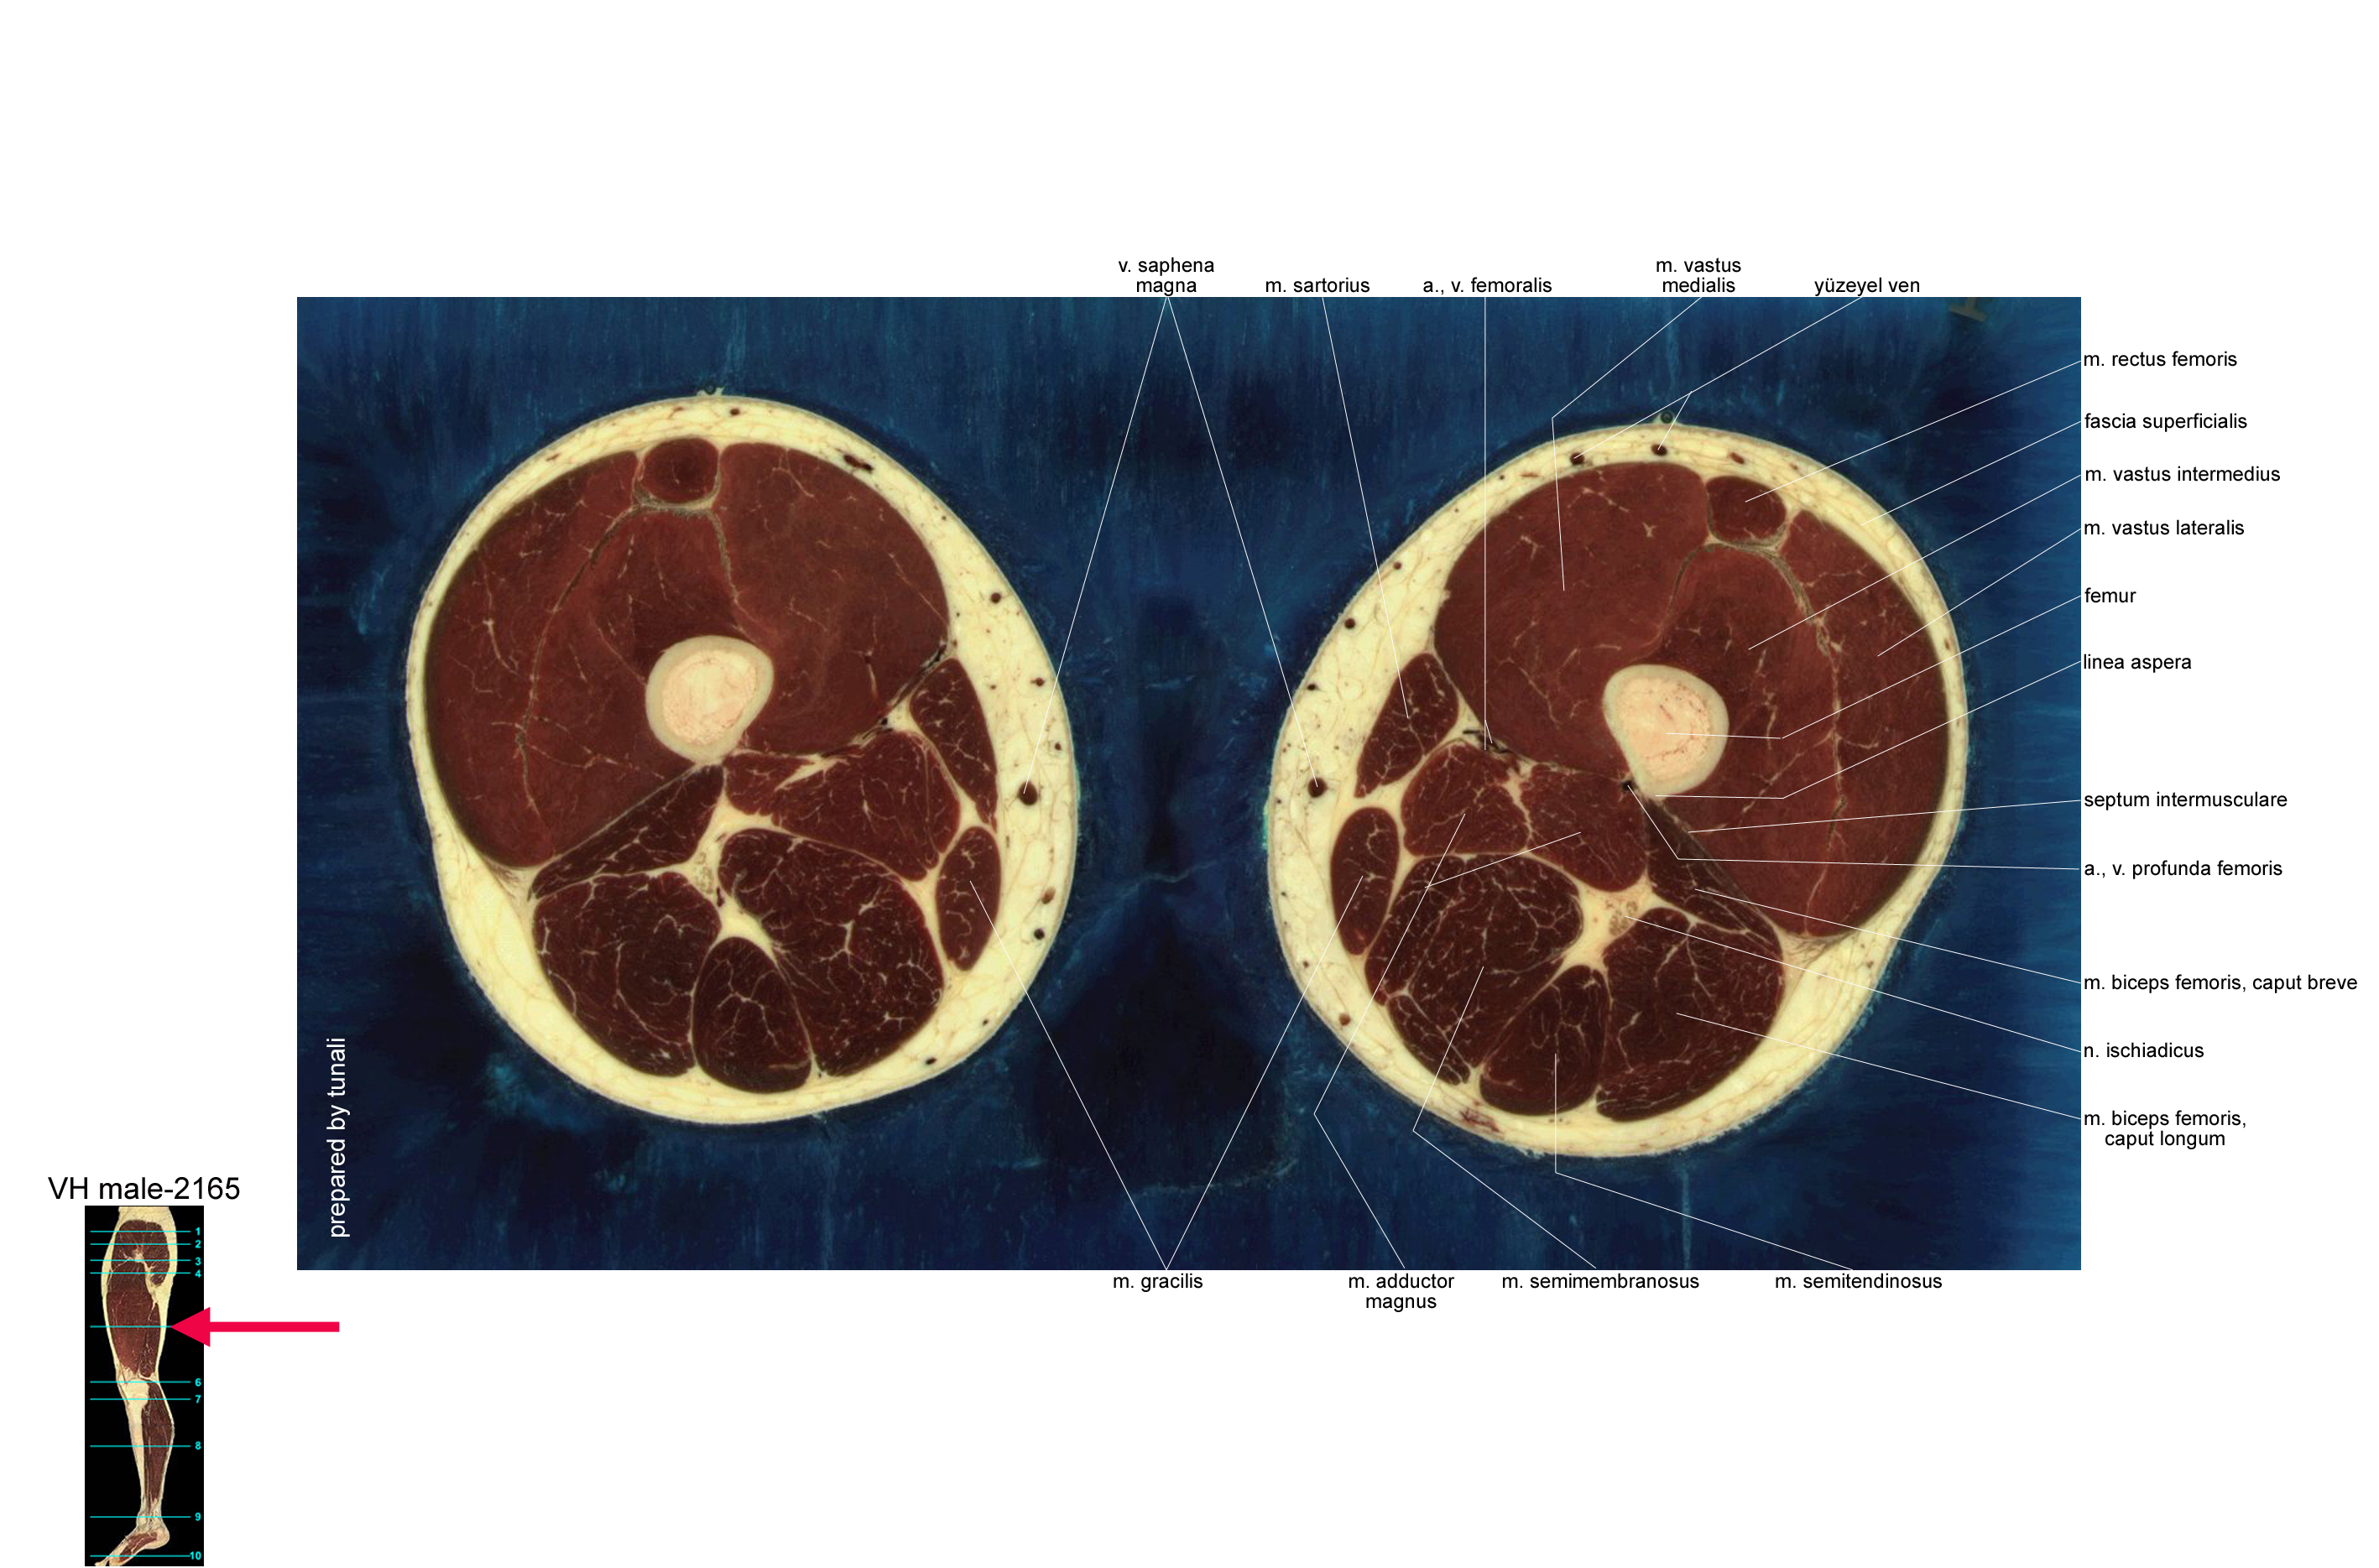

kesitsel anatomi • cross-sectional anatomy

kesitsel anatomi

iskelet sistemi kesitsel anatomisi. read more.....

click the images for the higher resolution versions